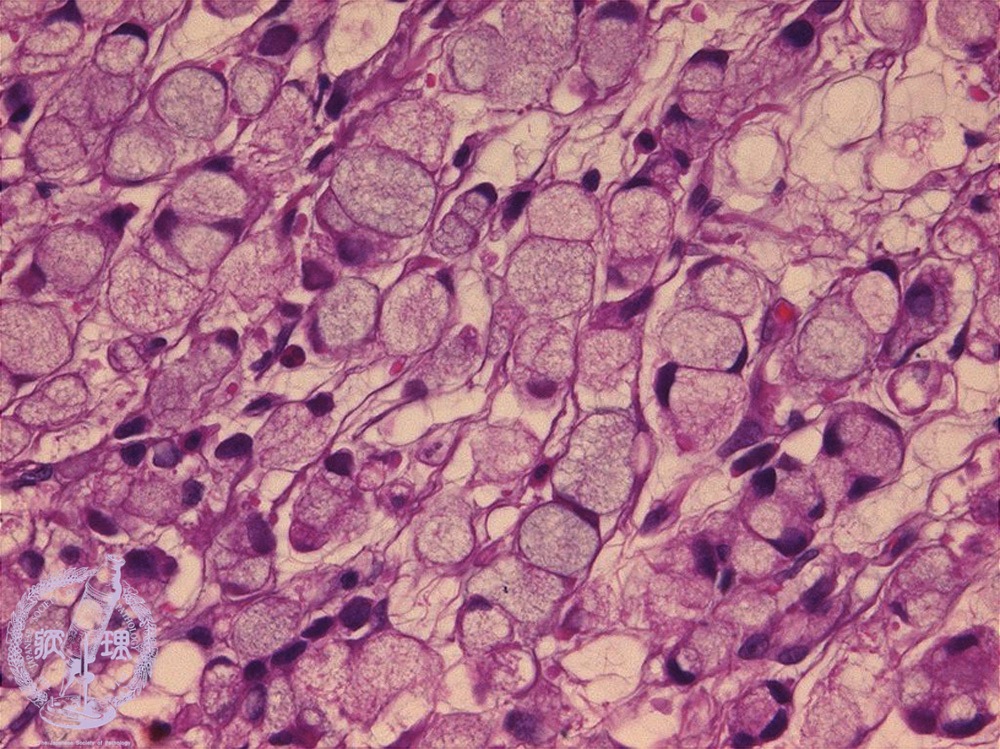

Microscopic appearance (H&E stain, high power): In signet-ring cell carcinoma the tumor cells demonstrate accumulation of cytoplasmic mucin.